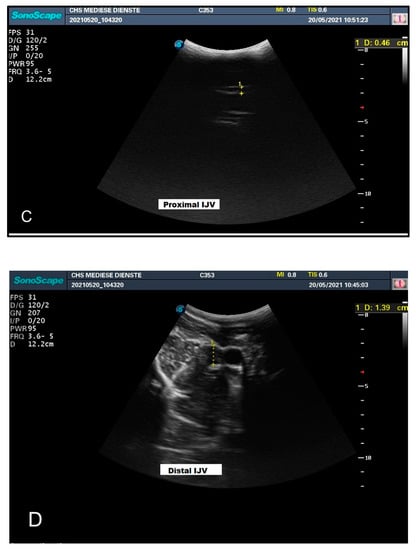

3.1. Experiment Part 1: Measurement of the Carotid Artery and Jugular Vein in an Upright Posture

| Head Position | Diameter (mm) CCA | Diameter (mm) IJV | ||

|---|---|---|---|---|

| Proximal | Distal | Proximal | Distal | |

| Head Up | 13.8 | 13.9 | 4.6 | 13.9 |

| Head Down | 13.1 | 13.3 | 12.6 | 16.1 |